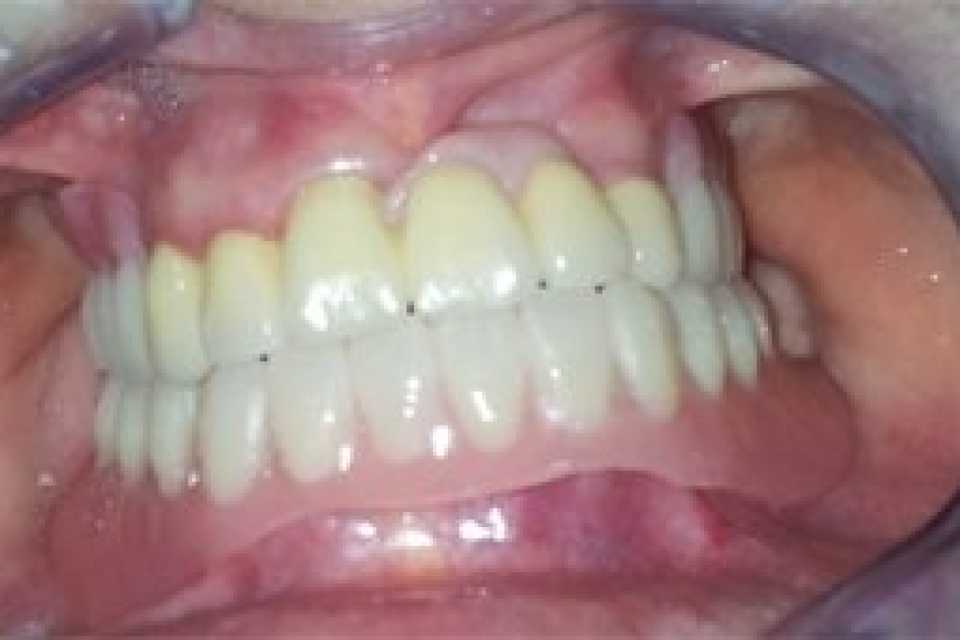

Proteza scheletata superioara pe telescoape si inferioara pe capse

Cazul 21: Proteze scheletate cu sisteme speciale de prindere

Protezele scheletale cu sisteme speciale de prindere reprezintă soluții de tratament care necesită înaltă specializare atât a medicului stomatolog, cât și a tehnicianului dentar, fiind recomandate în special pacienților cu edentații extinse, însă care prezintă încă suficienți dinți naturali rămași pe care se pot realiza astfel de lucrări dentare.